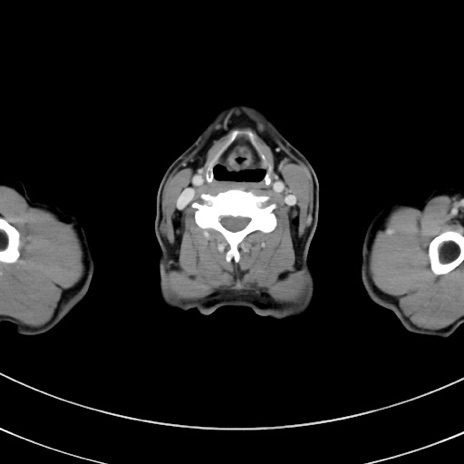

症例8(横断像)

【症例】 60歳代男性

【主訴】 黒色吐物

【現病歴】 4日前から嘔気自覚、2日前の朝食後にも嘔気あり、自分で手で嘔吐反射起こし嘔吐したところ血が混ざっていたため受診。

【既往歴】 5年前汎発性腹膜炎を伴う急性虫垂炎で手術、高血圧、前立腺肥大症、高脂血症

【身体所見】 腹部正中に手術癩痕あり 腹部平坦・軟圧痛なし膨満感あり

【データ】WBC 8400、CRP 4.54